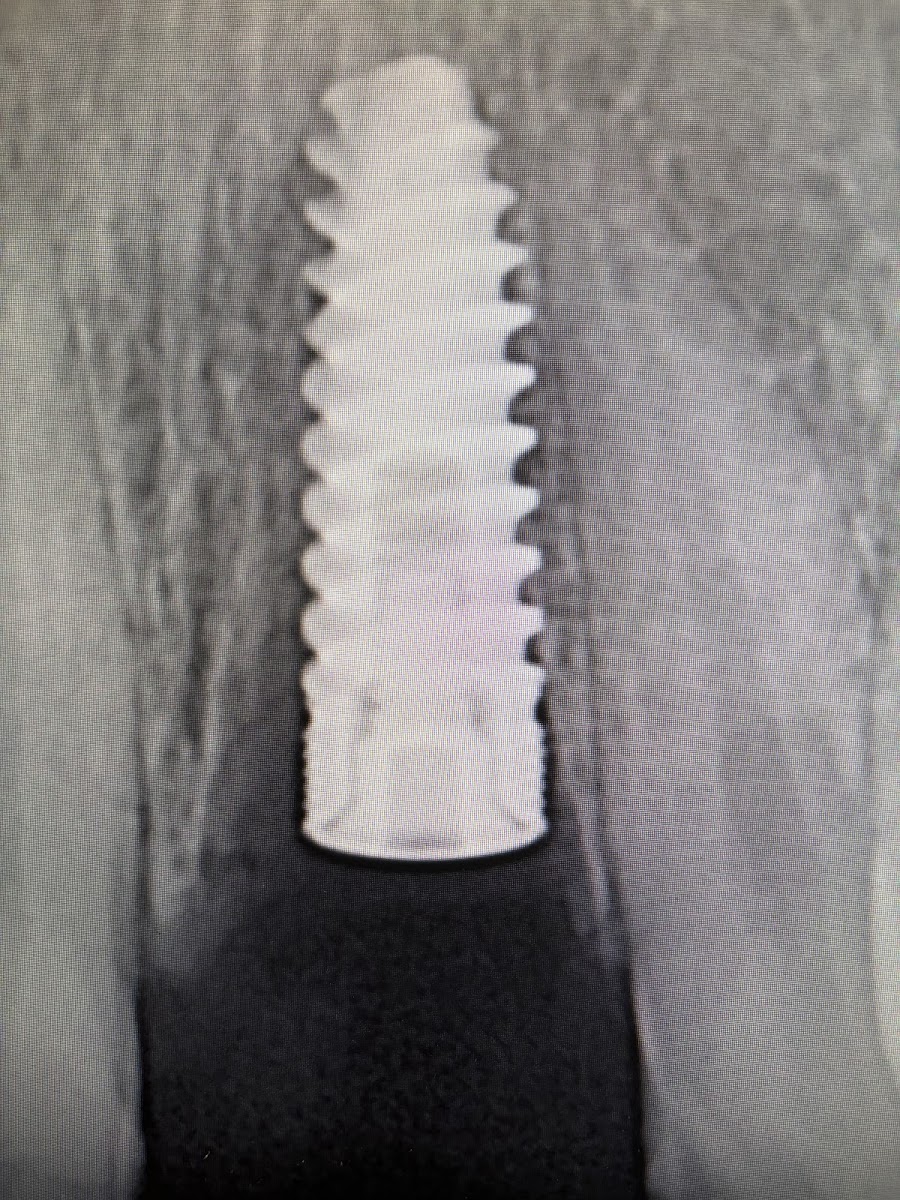

The journey of The Tribeca Dentist traces back to Dr. Saggese's distinguished academic and professional path. A graduate of the University of Delaware with a B.A. in Biological Sciences and a Minor in Italian, he earned his Doctor of Dental Medicine (D.M.D.) from the prestigious Temple University Kornberg School of Dentistry. Honing his skills further, he completed a rigorous General Practice Residency at Woodhull Medical Center in Brooklyn, NY, where he gained expertise in endodontics, oral surgery, emergency dental care, and more. His passion for implantology led him to the NYU College of Dentistry Implantology Fellowship Program, culminating in his prestigious designation as a Fellow of the International Congress of Oral Implantologists (FICOI). This credential underscores his mastery in placing and restoring implants, a gold standard for tooth replacement that prevents bone loss and restores natural function.[2][5]

Expertise extends beyond Dr. Saggese to include specialists like Dr. Karen Lewkowitz, a Fellow of the American College of Dentists and orthodontic expert from Columbia University and NYU, enabling comprehensive solutions for all ages. Common patient needs—dental emergencies, bridges, cleanings, and implants—are met with precision, protecting bone health and boosting quality of life. Whether restoring a single tooth or overhauling an entire smile, the team delivers natural-looking, durable results that empower patients to eat, speak, and smile confidently.[1][4][5]